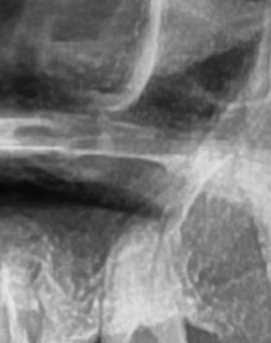

어금니 뒤 잇몸 부음의 문제는 사랑니가 원인이 되는 경우도 많은데 사랑니는 특히 현대인들의 경우 제대로 나오지 못하고 매복되는 경우가 많으며 완전히 나오지 않은 사랑니는 잇몸 속에서 자라면서 주변 잇몸을 자극할 수 있고, 일부만 노출되면 음식물이 끼면서 염증이 생기기도 하며 특히 어금니 뒤쪽 잇몸이 붓고 지속적으로 불편함을 느낀다면 사랑니로 인한 염증을 의심해 볼 수 있어요. 사랑니로 인한 문제의 경우 단순한 소염제나 구강 세정제로 해결되지 않고, 사랑니를 발치해야 잇몸 염증이 해결되는 경우가 많이 있어요

가장 주의해야 하는 문제 중에 치주염이 진행되면 어금니 뒤쪽뿐만 아니라 전체적인 잇몸이 약해질 수 있어요. 치주염은 치아를 둘러싸고 있는 조직이 손상되는 질환인데 특히 잇몸이 자주 붓거나 피가 나는 경우에는 치주염이 진행되고 있는 신호일 수 있기 때문에 단순한 잇몸 붓기로 넘기지 않는 것이 좋으며 치료를 받지 않으면 결국 치아를 지탱하는 뼈가 약해지고, 심한 경우에는 치아가 흔들리거나 빠질 수도 있었어요.

결론적으로는 통증이 심하거나 염증이 오래 지속되는 경우에는 치과를 방문해서 정확한 진단을 받는 것이 중요한데 단순한 잇몸 염증이라면 치석 제거와 항생제 치료로 호전될 수 있지만, 치주염이 진행된 경우라면 보다 적극적인 치료가 필요할 수 있어요. 만약 사랑니로 인해 잇몸이 자꾸 붓는다면 사랑니 발치를 고려해야 하겠고 사랑니가 완전히 매복되어 있다면 수술적인 방법으로 제거해야 할 수도 있어요. 특히 반복적으로 붓는다면 사랑니 검사를 받아보거나, 치과에서 정밀 검진을 통해 치주 상태를 확인하는 것이 필요하다는 점에서 어금니 근처의 잇몸이 반복적으로 불편하다면 꼭 치과를 찾아보시길 바라고 있어요